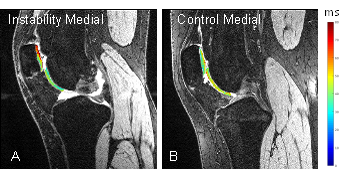

Optimizing Non-Contrast Magnetic Resonance Imaging (MRI) Sequences for Knee Synovitis

Inflammatory arthritis (IA) is a group of diseases that includes rheumatoid arthritis (RA), psoriatic arthritis (PsA), and ankylosing spondylitis (AS). Joints with IA often have proliferative, hyperplastic synovitis that can cause significant cartilage loss, bone erosion that can lead to progressive physical disability. Proliferative synovitis is an important indicator of disease activity since it drives the inflammatory processes. Imaging plays a key role in diagnosis and measurement of disease burden and treatment response. While radiography and ultrasound are very useful, only magnetic resonance imaging (MRI) provides an overview of the entire joint. Currently, intravenous (IV) contrast is used to visualize synovitis on MRI and differentiate it from joint fluid, and dynamic contrast-enhanced (DCE) MRI is considered the imaging gold standard. Non-contrast MRI techniques, e.g. diffusion-weighted MRI, can assess IA synovitis, however they suffer from low spatial resolution limiting their value for small joints such as the wrist. While cartilage and other joint structures have been extensively studied with MR relaxation time mapping, joint fluid, inflammatory synovitis, and other intra-articular tissues have not been investigated intensively. T1 mapping was recently used to delineate knee synovitis in OA patients. However, there are no published T1 or T2 relaxation time maps for synovitis in patients with knee IA. At 1.5T, we developed a semi-automated segmentation method for quantifying inflamed synovitis using DCE MRI. We propose to optimize the acquisition parameters of non-contrast 3D FSE (3D SPACE) for the robust clinical evaluation of inflammatory synovitis.